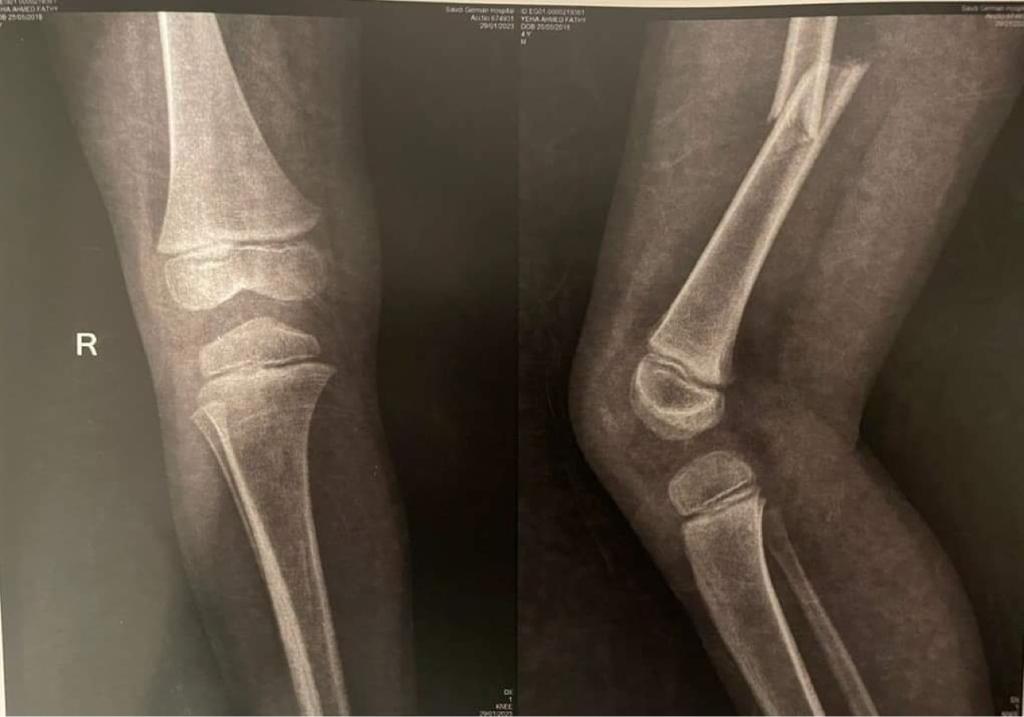

وأخبرت المستشفى والدة الطفل أنه مصاب بكسر في عظمة الفخذ، ويحتاج إلى عملية جراحية، ومن بعدها علاج طبيعي ويحتاج إلى عملية أخرى.

وقال والد الطفل أحمد فتحي لـ القاهرة 24: أصيب الطفل في كسر في الفخذ، وأجريت له عملية تركيب مسامير، وسيبدأ الطفل في رحلة العلاج الطبيعي، وبعد 4 شهور سيتم إجراء عملية أخرى له.